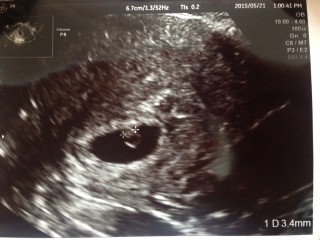

待望の3人目を妊娠して6週3日で胎芽は2mmくらいでしたが2mmでもチカチカとしっかり心拍確認できました!何回妊娠しても心拍確認はほんとドキドキします

胎嚢の中の胎芽の真ん中が、チカチカして心拍確認が出来た時は本当に安堵しました。一度繋留流産経験していたので、夢にまでみた瞬間でした。胎嚢の大きさは23.4mmです。